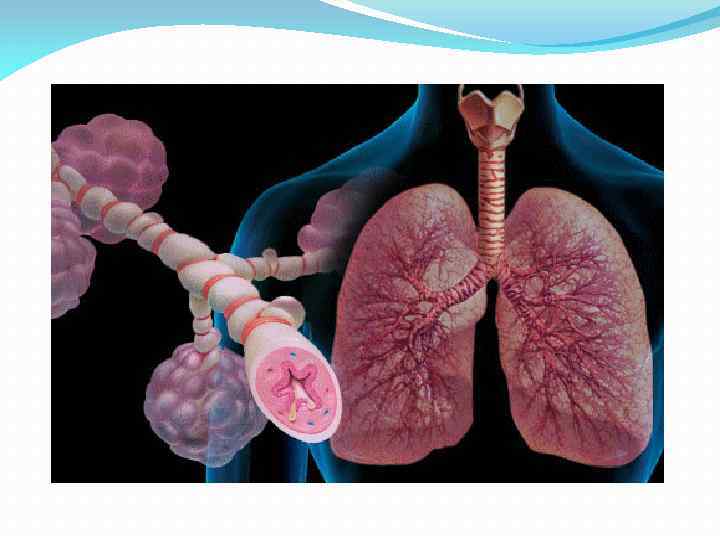

ДН – ситуация, при который организм не в состоянии поддерживать в крови парциальное давление или углекислого газа, адекватное тканевому метаболизму. В механизме развития острой дыхательной недостаточности ведущую роль играют нарушения вентиляционных и мембранных процессов газообмена.

ДН – ситуация, при который организм не в состоянии поддерживать в крови парциальное давление или углекислого газа, адекватное тканевому метаболизму. В механизме развития острой дыхательной недостаточности ведущую роль играют нарушения вентиляционных и мембранных процессов газообмена.

Причины К развитию дыхательной недостаточности (ДН) могут приводить повреждения аппарата внешнего дыхания на различных уровнях: центральная нервная система и дыхательный центр – например, передозировка наркотических препаратов, нарушение мозгового кровообращения, повреждения головного мозга и дыхательного центра; нервно-мышечная система — различные неврологические и инфекционные заболевания, повреждающие нервную систему и нарушающие механизм передачи импульсов к дыхательным мышцам (например, миастения, ботулизм); грудная клетка – сколиоз (искривление позвоночника), ожирение, пневмоторакс (попадание воздуха в плевральную полость – полость, образованную листками плевры, внешней оболочки легких), наличие патологической жидкости в плевральной полости; дыхательные пути – например, отек гортани, инородное тело в бронхе, заболевания, характеризующиеся хроническим воспалительным процессом в бронхах (бронхиальная астма, хроническая обструктивная болезнь легких (ХОБЛ)); альвеолы (конечное звено дыхательной системы, в котором осуществляется газообмен) – например, пневмония (воспаление легких), отек легких, заболевания, характеризующиеся разрастанием в легких соединительной ткани (фиброзирующие альвеолиты, саркоидоз).

Причины К развитию дыхательной недостаточности (ДН) могут приводить повреждения аппарата внешнего дыхания на различных уровнях: центральная нервная система и дыхательный центр – например, передозировка наркотических препаратов, нарушение мозгового кровообращения, повреждения головного мозга и дыхательного центра; нервно-мышечная система — различные неврологические и инфекционные заболевания, повреждающие нервную систему и нарушающие механизм передачи импульсов к дыхательным мышцам (например, миастения, ботулизм); грудная клетка – сколиоз (искривление позвоночника), ожирение, пневмоторакс (попадание воздуха в плевральную полость – полость, образованную листками плевры, внешней оболочки легких), наличие патологической жидкости в плевральной полости; дыхательные пути – например, отек гортани, инородное тело в бронхе, заболевания, характеризующиеся хроническим воспалительным процессом в бронхах (бронхиальная астма, хроническая обструктивная болезнь легких (ХОБЛ)); альвеолы (конечное звено дыхательной системы, в котором осуществляется газообмен) – например, пневмония (воспаление легких), отек легких, заболевания, характеризующиеся разрастанием в легких соединительной ткани (фиброзирующие альвеолиты, саркоидоз).